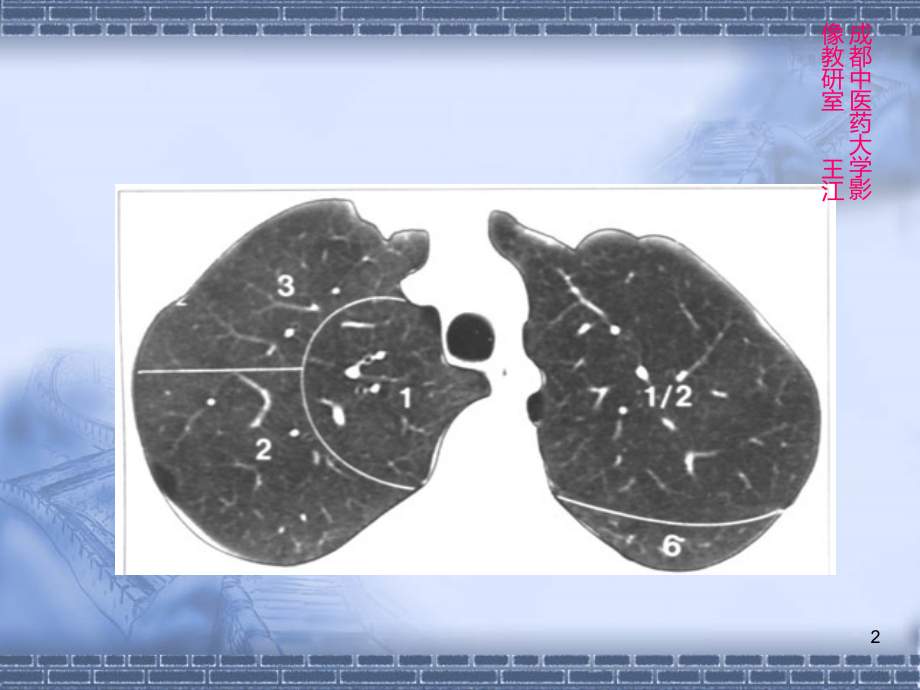

单击此处编辑母版标题样式,单击此处编辑母版文本样式,第二级,第三级,第四级,第五级,*,(三)各主要层面肺段,CT,表现,左上叶,上部,1+2,尖后段,3,前段,舌部,4,上段,5,下段,左下叶,6,背段,7+8,前内基底段,9,外基底段,10,后基底段,右上叶,1,尖段,2,后段,3,前段,右中叶,4,外段,5,内段,右下叶,6,背段,7,内基底段,8,前基底段,9,外基底段,10,后基底段,1,成都中医药大学影像教研室王江,2,成都中医药大学影像教研室王江,3,成都中医药大学影像教研室王江,4,水平裂层面,成都中医药大学影像教研室王江,5,成都中医药大学影像教研室王江,6,成都中医药大学影像教研室王江,7,成都中医药大学影像教研室王江,8,成都中医药大学影像教研室王江,9,成都中医药大学影像教研室王江,10,